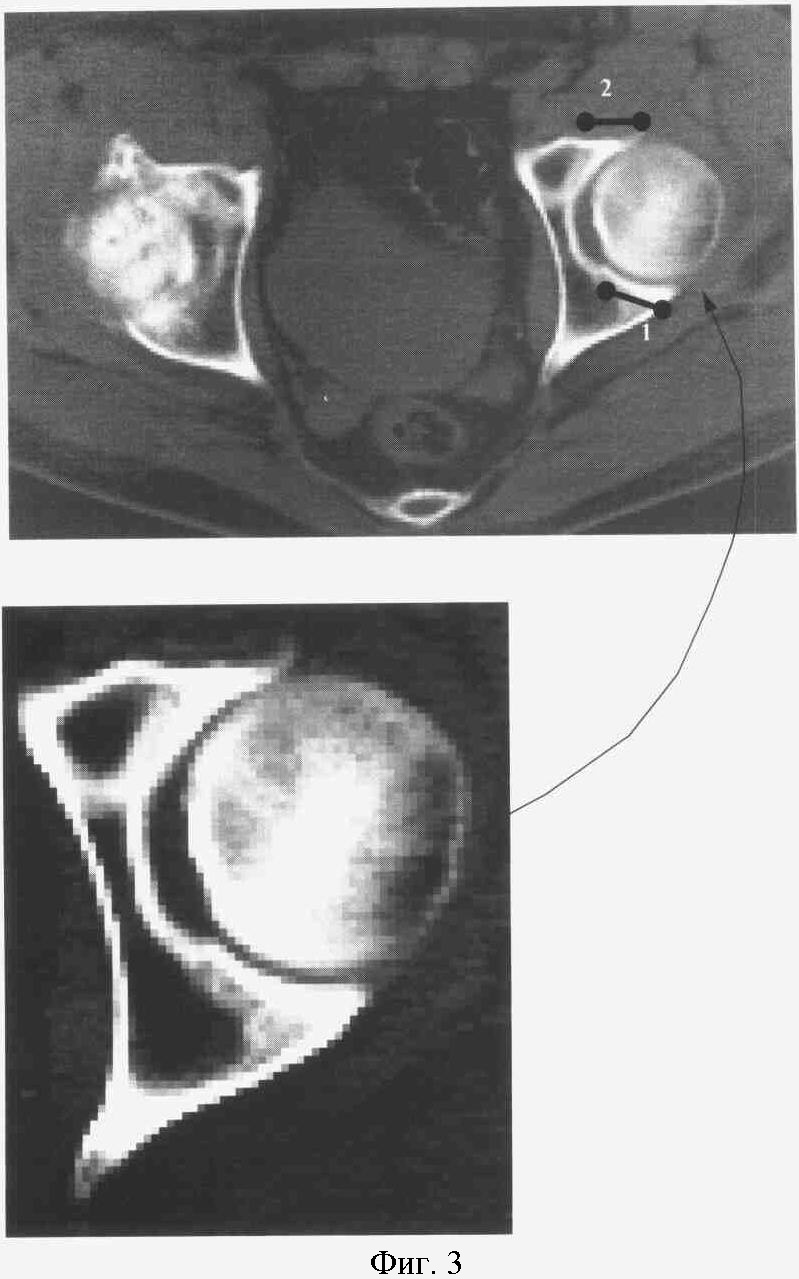

На фиг.3. представлен КТ срез на уровне ямки головки бедра.

Справа: 3-я стадия коксартроза с кистевидной перестройкой.

Слева: 2-я стадия коксартроза с локализацией участков компрессии в заднем и переднем отделах сустава (1).